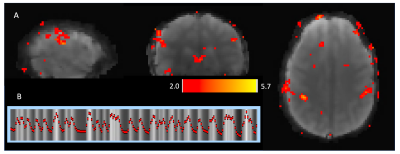

Figure 2: Setup of the SimulScan Acquisition with 1 mid-sagittal dynamic imageand 38 functional MRI slices. The acquisition interleaves a functional slice with the dynamic imaging. Note the dark line in the middle of the fMRI axial slice corresponding to the dynamic imaging plane.

The Partial Separability (PS) model acquires a temporal navigator at each time point and then only one shot of the imaging data that highly undersamples (k, t)-space. After the temporal basis is determined from the temporal navigators with very high temporal resolution, the corresponding spatial basis of the PS model can be determined from the sparsely sampled imaging data across the time series. For this work, we designed a navigator that was one shot of a 24-shot, 64-matrix size spiral-in navigator. This was immediately followed by acquiring one shot of a 24-shot, 128-matrix size spiral-out imaging data. The navigator and imaging readouts were concatenated together as shown in Figure 1. SimulScan proceeds by acquiring one of these dynamic shots in between each 2D functional MRI slice (see Figure 2). The fMRI was a spiral-in, TE = 25 ms, 96 matrix size trajectory with a reduction factor of 2, reconstructed by SENSE5,6. We used a 38-slice fMRI acquisition with 3 mm slice thickness, fat sat on, resulting in an overall TR (fMRI slice and dynamic shot) of 76.6 ms, 13 fps dynamic imaging, and an overall TR for 38 slice fMRI data of 2.9 s. A healthy adult subject was scanned for 9.5 minutes and asked to tap their tongue several times during the course of the run, without cue and at their own pace, trying to get at least 20 taps in the run.